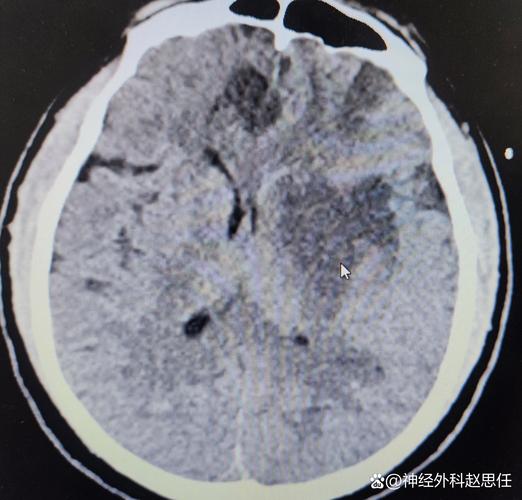

- 影像学检查:头颅CT平扫是首选的快速检查,可以快速排除脑出血,并初步判断梗塞的范围和是否有早期脑水肿迹象,如果条件允许,会尽快进行头颅MRI+DWI,能更早、更准确地发现梗塞灶。